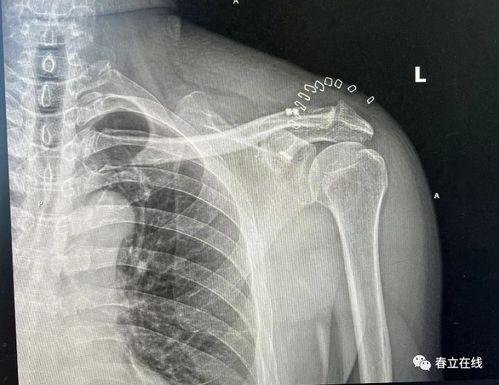

• 肩锁关节脱位图片,图解与概述

最近有个朋友不小心摔了一跤,结果肩锁关节脱位了。这可真是让人心疼啊!肩锁关节脱位,听起来是不是有点陌生?别急,今天我就带你来详细了解一番,让你对这个神秘的关节有个清晰的认识。而且,我还准备了一些肩锁关节脱位的真实图片,让你直观地感受一下这个问题的严重性。肩...